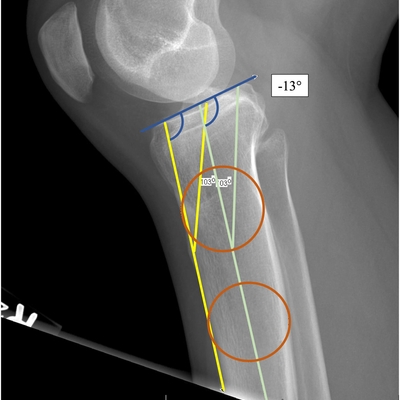

Click on an image below to view more info.